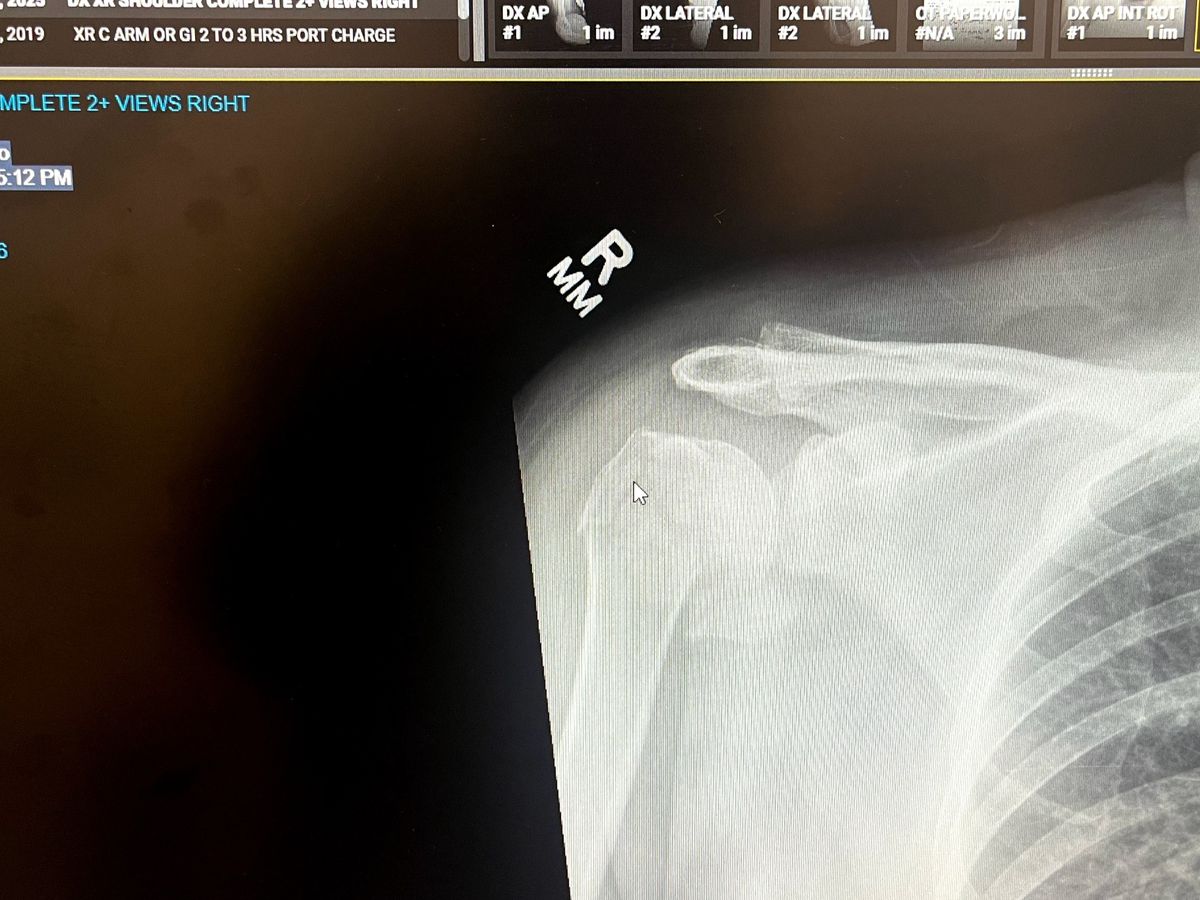

I recently fell and fractured my right shoulder requiring a partial replacement. Thankfully insurance is covering the surgery but I will be out of work for sometime and could use some help with rent, food and other bills. The basics until I am medically cleared to return to work (with limitations). It's going to be a difficult few months with physical therapy, etc.